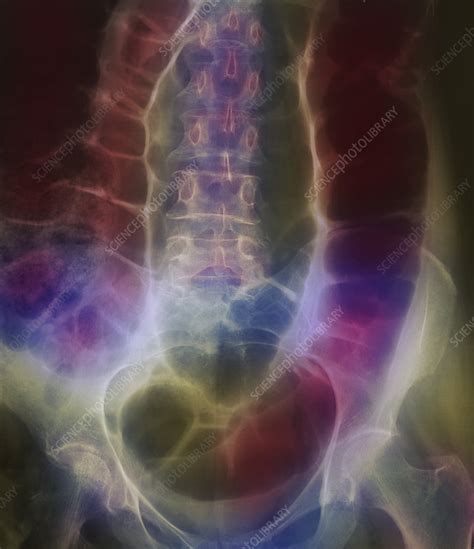

Twisted Colon Photograph by Science Photo Library